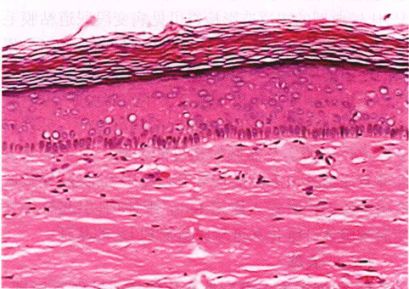

LS具有典型的组织学表现,包括青苔状间期皮炎、表皮萎缩和角化过度,伴有或不伴有表皮基底细胞层空泡变性。早期表现为基底层空泡变性,上皮下胶原的透明化,真皮上部弹性纤维减少,基底膜下血管扩张。在年长的病变, 显示透明状真皮内单核细胞数量减少,单核细胞分散成片状。

明显的上皮层过度角化,X40;图片来源于徐月敏著